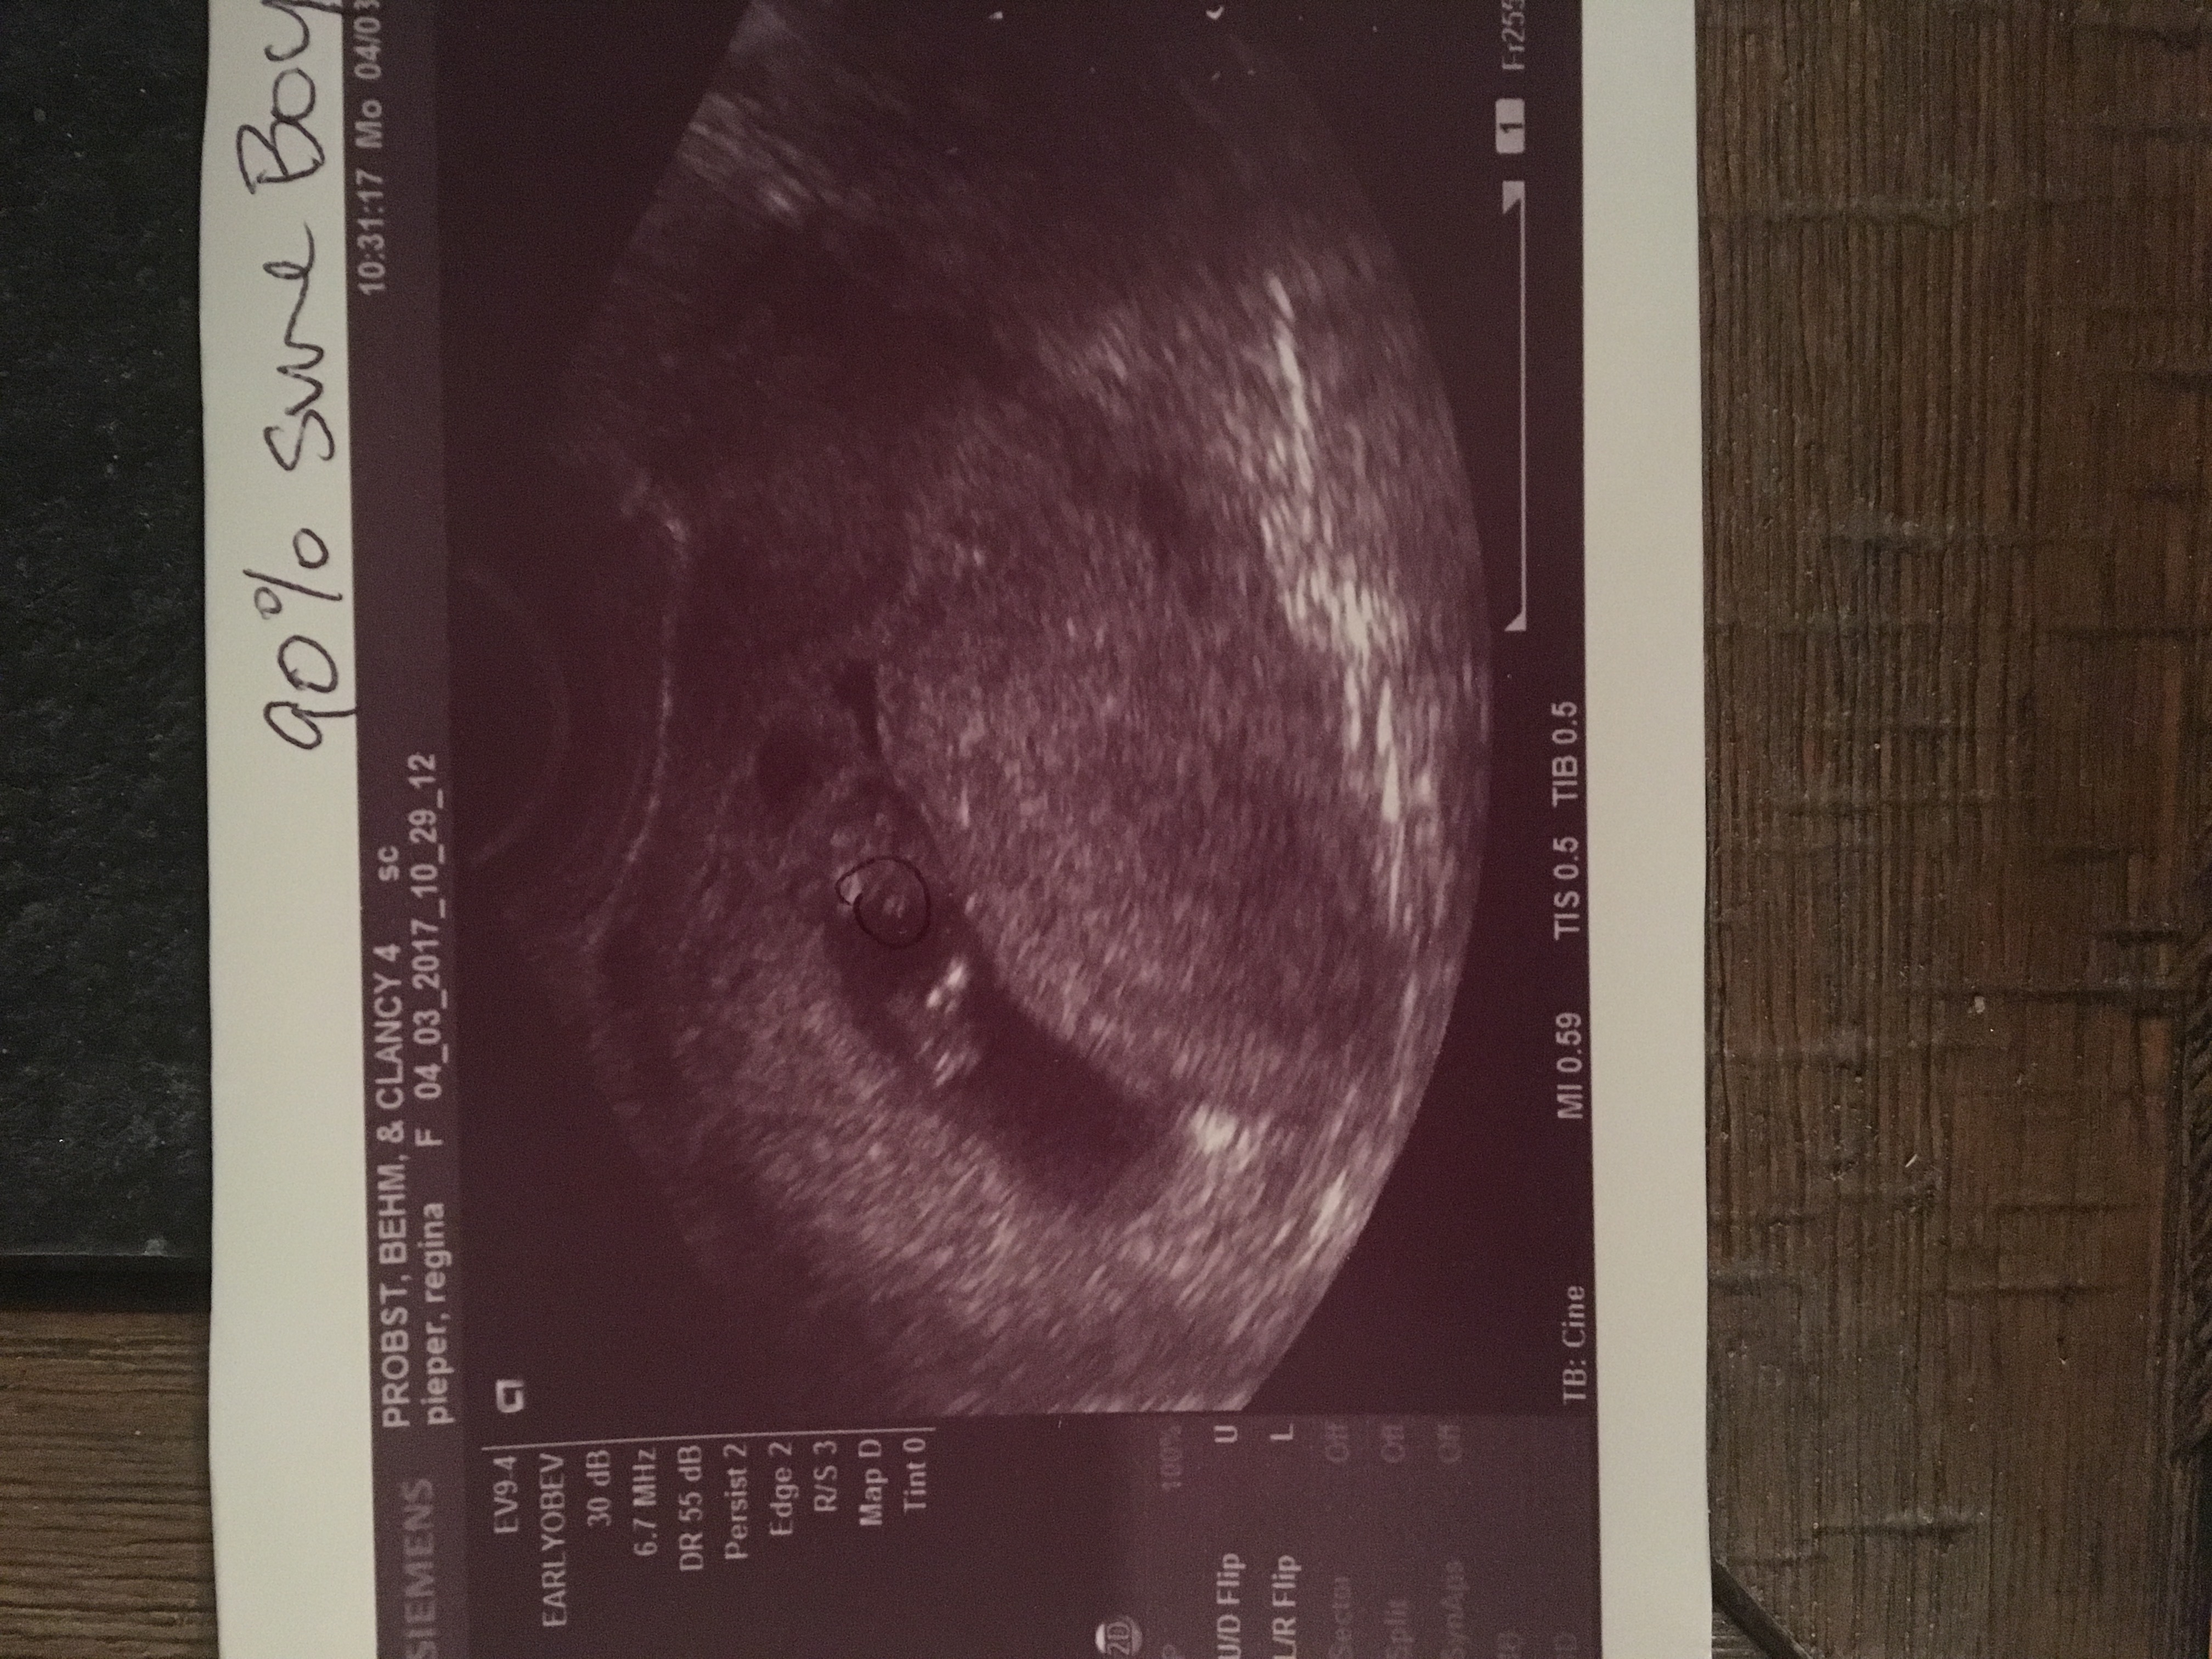

Boy or girl???

This is my ultrasound picture from 11 weeks and 2 days. My OB told me she was 90% sure it's a boy. I've read about the nub theory, but this looks like a potty shot. We have a boy already so I was kind of secretly dreaming for a baby girl- I have four sisters and they all have had only boys so we've never had a little girl in the family. I know I will love and adore another boy! But I just wanted others opinions. Thanks so much!!!

If you zoom you can see where she circled with pen what she believes are the boy parts

11+2 is too early for gender guessing. Did you get any other pics than this one?

That's what I was thinking too! This was the only picture she gave us! I just didn't know if I was in denial since part of me wants a girl so bad haha! or if there was something I was missing.